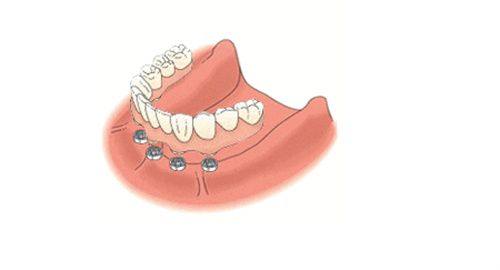

当骨结合完成后,就可以进行修复体安装了。医生会先取模,根据你的口腔情况制作一个个性化的牙冠,然后采用螺丝固位或者粘接固位的方式把牙冠安装到种植体上。如果是全口种植,可能还会涉及到即刻负重或者All - on - 4等特殊技术,这些技术能让你更快地修复牙齿的功能。